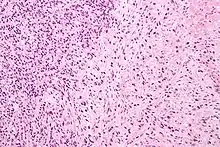

Gleason 3

Gleason 3 is a clearly infiltrative neoplasm, with extension into adjacent healthy prostate tissue. The glands alternate in size and shape, and are often long/angular. They are usually small/micro-glandular in comparison to Gleason 1 or 2 grades. However, some may be medium to large in size. The small glands of Gleason 3, in comparison to the small and poorly defined glands of pattern 4, are distinct glandular units. Mentally you could draw a circle around each of the glandular units in Gleason 3.[4][7]